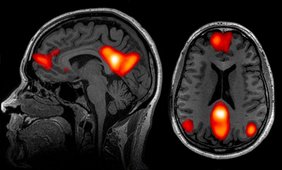

Was passiert, wenn 70 Forschungsteams aus aller Welt unabhängig voneinander denselben Datensatz analysieren, um dieselben Hypothesen zu prüfen? Diese Frage beantwortet erstmals eine internationale Studie, die von den Ökonomen Michael Kirchler, Jürgen Huber und Felix Holzmeister vom Institut für Banken und Finanzen der Universität Innsbruck mitinitiiert wurde. Gemeinsam mit Forschern des California Institute of Technology, der Stanford University, der Stockholm School of Economics und der Universität Tel Aviv haben sie rund 200 Wissenschaftlerinnen und Wissenschaftler eingeladen, den gleichen MRT-Datensatz zu analysieren und neun Forschungshypothesen zu überprüfen. Die Daten stammen aus einem Experiment in Tel Aviv, bei dem die Hirntätigkeit von 108 Probanden mit Hilfe von Funktioneller Magnetresonanztomographie aufgezeichnet wurde, während sie ökonomische Entscheidungen trafen. Das Verfahren zeigt mit hoher räumlicher Auflösung jene Hirnareale an, die während der Messung aktiv sind. Die neurowissenschaftlichen Forschungsteams wurden gebeten, diese Daten mit ihren etablierten Analyseverfahren dahingehend zu untersuchen, ob es Hinweise für einen Zusammenhang zwischen der Aktivität von Teilen des Gehirns und bestimmten Aspekten ökonomischer Entscheidungssituationen gibt.